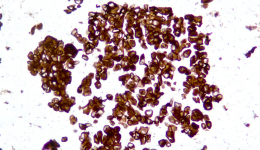

CLDN18.2 +++ 石蠟撈片標(biāo)準(zhǔn)品

Description CLDN18.2是Claudin蛋白質(zhì)家族的一員,位于細(xì)胞膜表面,Claudin18.2(CLDN18.2)表達(dá)具有特異性。其作為Claudins蛋白的一個(gè)亞型,在正常組織中僅表達(dá)于分化的胃黏膜上皮細(xì)胞。在胃癌、食管癌和胰腺癌等多種腫瘤中表達(dá),并且不僅限于原發(fā)病灶,在轉(zhuǎn)移灶中也有表達(dá)。目前臨床研究中使用的檢測方法均為免疫組化。

IHC染色結(jié)果